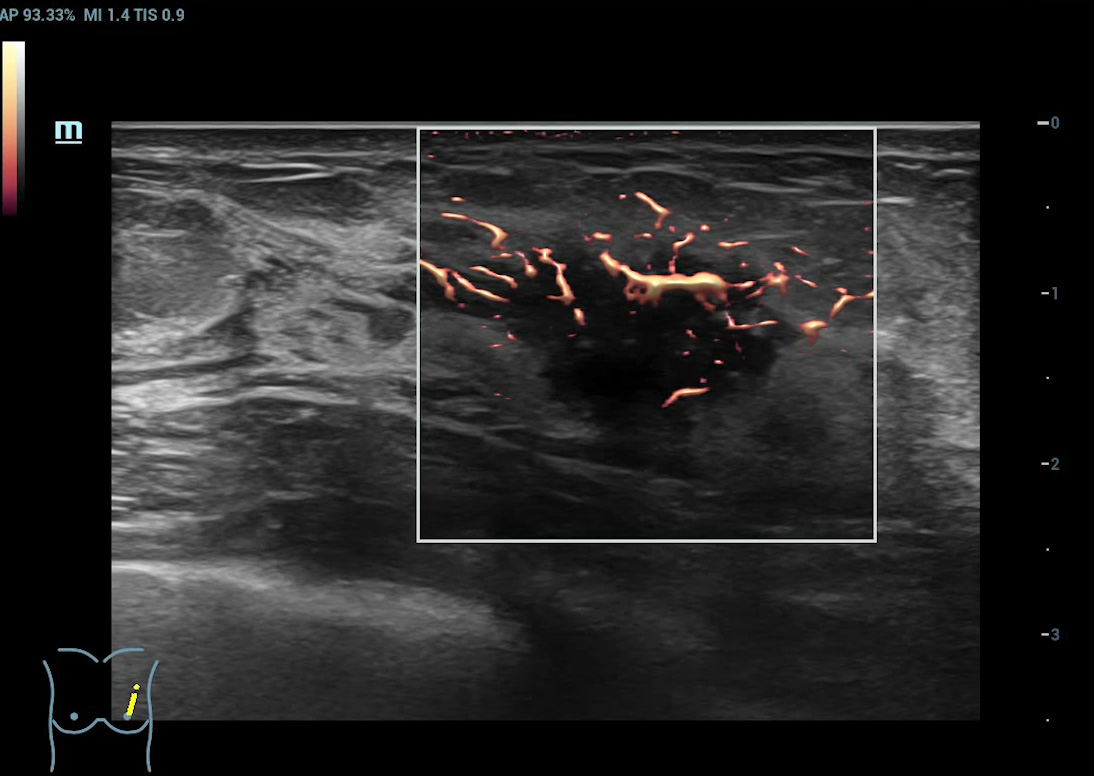

Ultra-Micro-angiografie (UMA)

UMA verbetert het diagnostische vertrouwen door de zichtbaarheid van de bloedstromen uit te breiden tot op het kleinste vaatniveau, met een superieure gevoeligheid en resolutie van de bloedstroom.

pUMA Borstmassa

Beeldengalerij

Borstmassa cUMA

Borstmassa